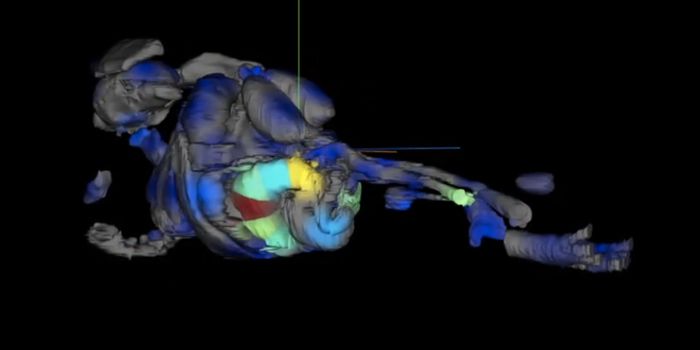

AUG 26, 2021MicrobiologyScientists have used a mouse model to visualize the progression of a SARS-CoV-2 infection as it led to sometimes fatal c ...